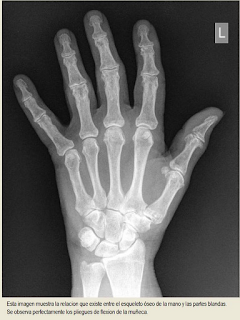

TRES ESPACIOS ANATÓMICOS DEL CARPO. Vemos en esta radiografía centrada en la cara anterior del carpo los puntos, áreas o zonas en que cada una de esas tres teorías ubican el traspasar del clavo por la muñeca . Permitirían fijar con toda garantía al travesaño de la cruz , el miembro superior de un crucificado , sin que cayera al estar sometido a fuerzas de tracción y a su propio peso y por tanto desgarrarse las partes blandas , si se hubiera clavado al madero en el centro de la palmas de las manos . Quizás para este propósito , lo más adecuado era clavar el antebrazo pasando el clavo a través del Espacio de Destot del carpo .

De abajo hacia arriba , en la imagen radiológica , tenemos : El cúbito y el radio , encima el carpo con sus huesecillos,los cinco metacarpianos y las falanges de los dedos de la mano .

Como observamos en estas imágenes en las que se aprecia tanto el esqueleto como las partes blandas, la palma de la mano comprende huesos del carpo, los cinco metacarpianos y parte de las falanges de los dedos a excepción del pulgar.

Al igual que observamos que la muñeca comprende los huesos del carpo, su articulación con los metacarpianos de un extremo y su articulación con el radio del otro extremo. |